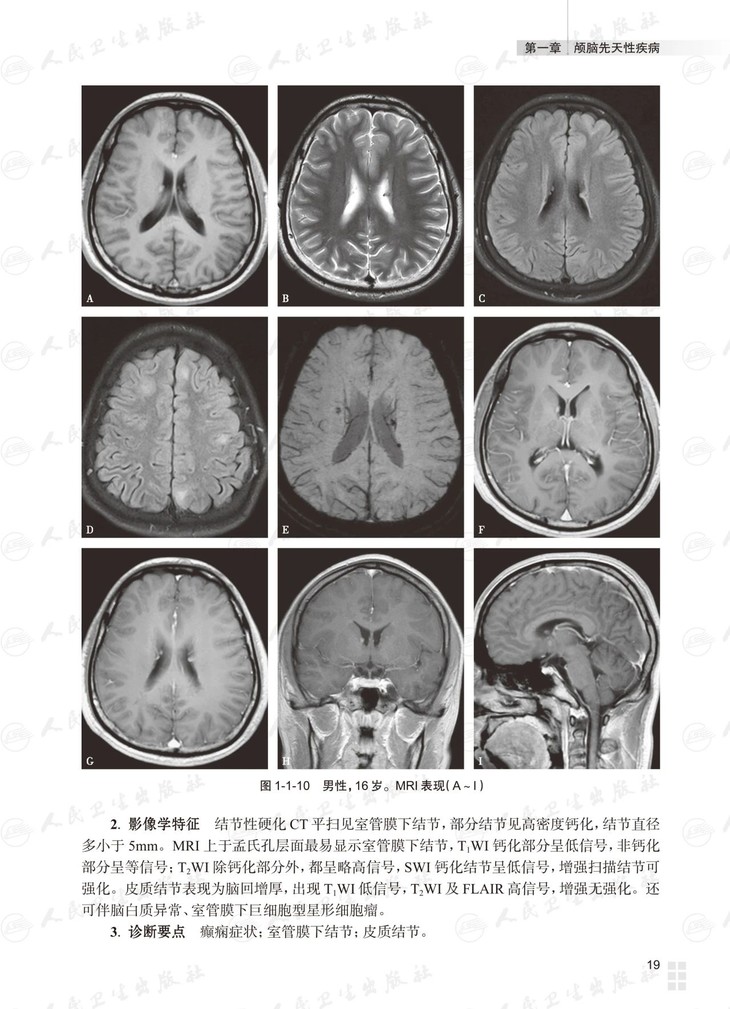

本书总论部分介绍多模态脑功能成像技术及临床应用。各论分为三篇:基础篇为常见颅脑疾病多模态磁共振成像典型病例分析,以复习为主,从疾病的临床与病理入手,解析影像学特征,提供影像诊断思路,最终给出诊断要点;进阶篇为各部位常见颅脑疾病多模态磁共振成像病例讨论,以考查为主,每章讨论颅脑同一部位的多个病例,附有多模态磁共振图像的征象分析、诊断及诊断要点,最后以思维导图的形式展示对该部位疾病的影像诊断思路;高级篇是多模态磁共振成像在颅脑疾病鉴别诊断中的应用,重在对功能成像技术进行横向比较,作出鉴别诊断。